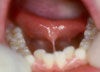

Es la especialidad de la Odontología que se encarga del tratamiento de la patología bucal en los pacientes en edad infantil y juvenil mientras presentan la dentición decidua (de leche), mixta o permanente. Los niños y los jóvenes deben seguir controles preventivos, al menos una vez al año, con el fin de diagnosticar de forma precoz los posibles problemas que puedan aparecer para efectuar inmediatamente los tratamientos lo menos agresivos posibles.

Los procedimientos que se hacen a estos pacientes son parecidos a los que se realizan a los pacientes adultos aunque en la dentición temporal y junto con las características psicológicas de los niños y jóvenes, requieren unas consideraciones específicas en relación con las técnicas y el manejo del paciente que es fundamental para poder ejecutar la opción terapéutica indicada sin producir dolor o malestar.